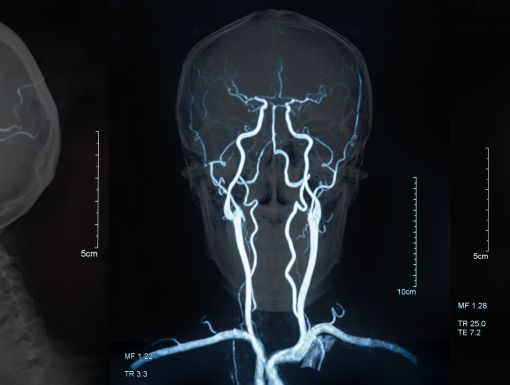

When it comes to a stroke, every second counts. Many of us may not be aware, but during a stroke, 1.9 million irreplaceable brain cells are lost each minute. And when brain cells die during a stroke, abilities controlled by that area of the brain are lost. These abilities include speech, movement and memory. Therefore, how a stroke patient is affected depends on where the stroke occurs in the brain and how much of the brain is damaged.

The most common symptoms of a stroke are: trouble speaking, trouble seeing, weakness on one side of the body or difficulty walking. If you or a loved one ever experiences one or several of these symptoms suddenly, please call 911.

Because time is of the essence during a stroke, hospitals having neurologists on call to diagnose and care for emergency stroke patients can be crucial to saving precious brain cells. However, most rural and many urban hospitals do not have neurologists on call, which can add even more panic to an already scary situation.